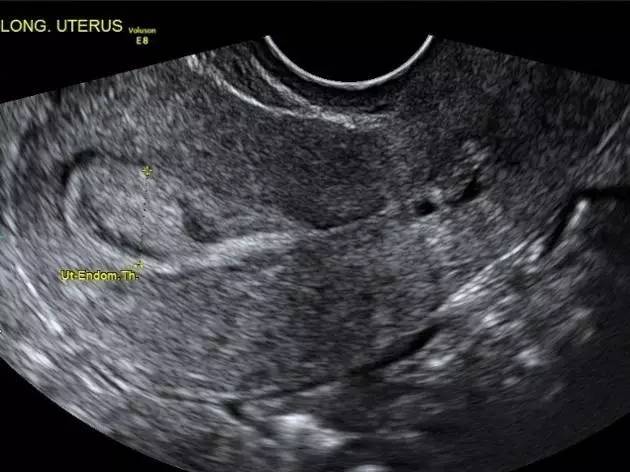

她的月经正常,但B超发现了一个子宫内膜息肉,0.8厘米,查体报告上书:建议手术切除。医生说得貌似也有道理,子宫腔里一共那么点儿地方,不把息肉弄走,孩子住哪儿?

子宫内膜息肉是一种常见的妇科疾病,是子宫局部内膜过度生长造成的,数量可单可多,直径可大可小,可有蒂可无蒂,息肉由子宫内膜腺体,间质和血管组成,患病率从7.8%到34.9%不等。

经阴道超声检查是最常用的诊断方法,最好安排在月经干净后进行,这时候子宫内膜薄,更容易发现息肉,有助于区分“息肉状子宫内膜”与“子宫内膜息肉”。诊断的金标准仍然是靠病理。

https://pic.wenwo.com/fimg/67021115289.jpg